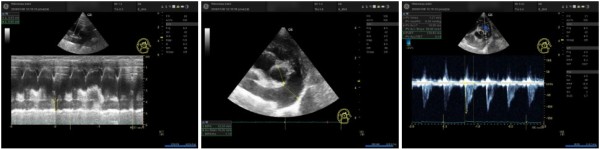

③ PA(폐동맥)의 혈류 역학

PA:Ao ratio: 1.15 (폐동맥이 대동맥보다 굵어짐, 정상은 < 1.0)

PV AT:ET ratio: 0.14 (폐동맥 혈류 분출 시간이 매우 짧아짐)

RVOT Velocity Pattern: Pattern 2 (Notching) 관찰. 이는 폐혈관 저항이 매우 높음을 시사하는 전형적인 소견입니다.

RPAD (Right Pulmonary Artery Distensibility): 0.25로 폐동맥의 탄성도 저하 확인.